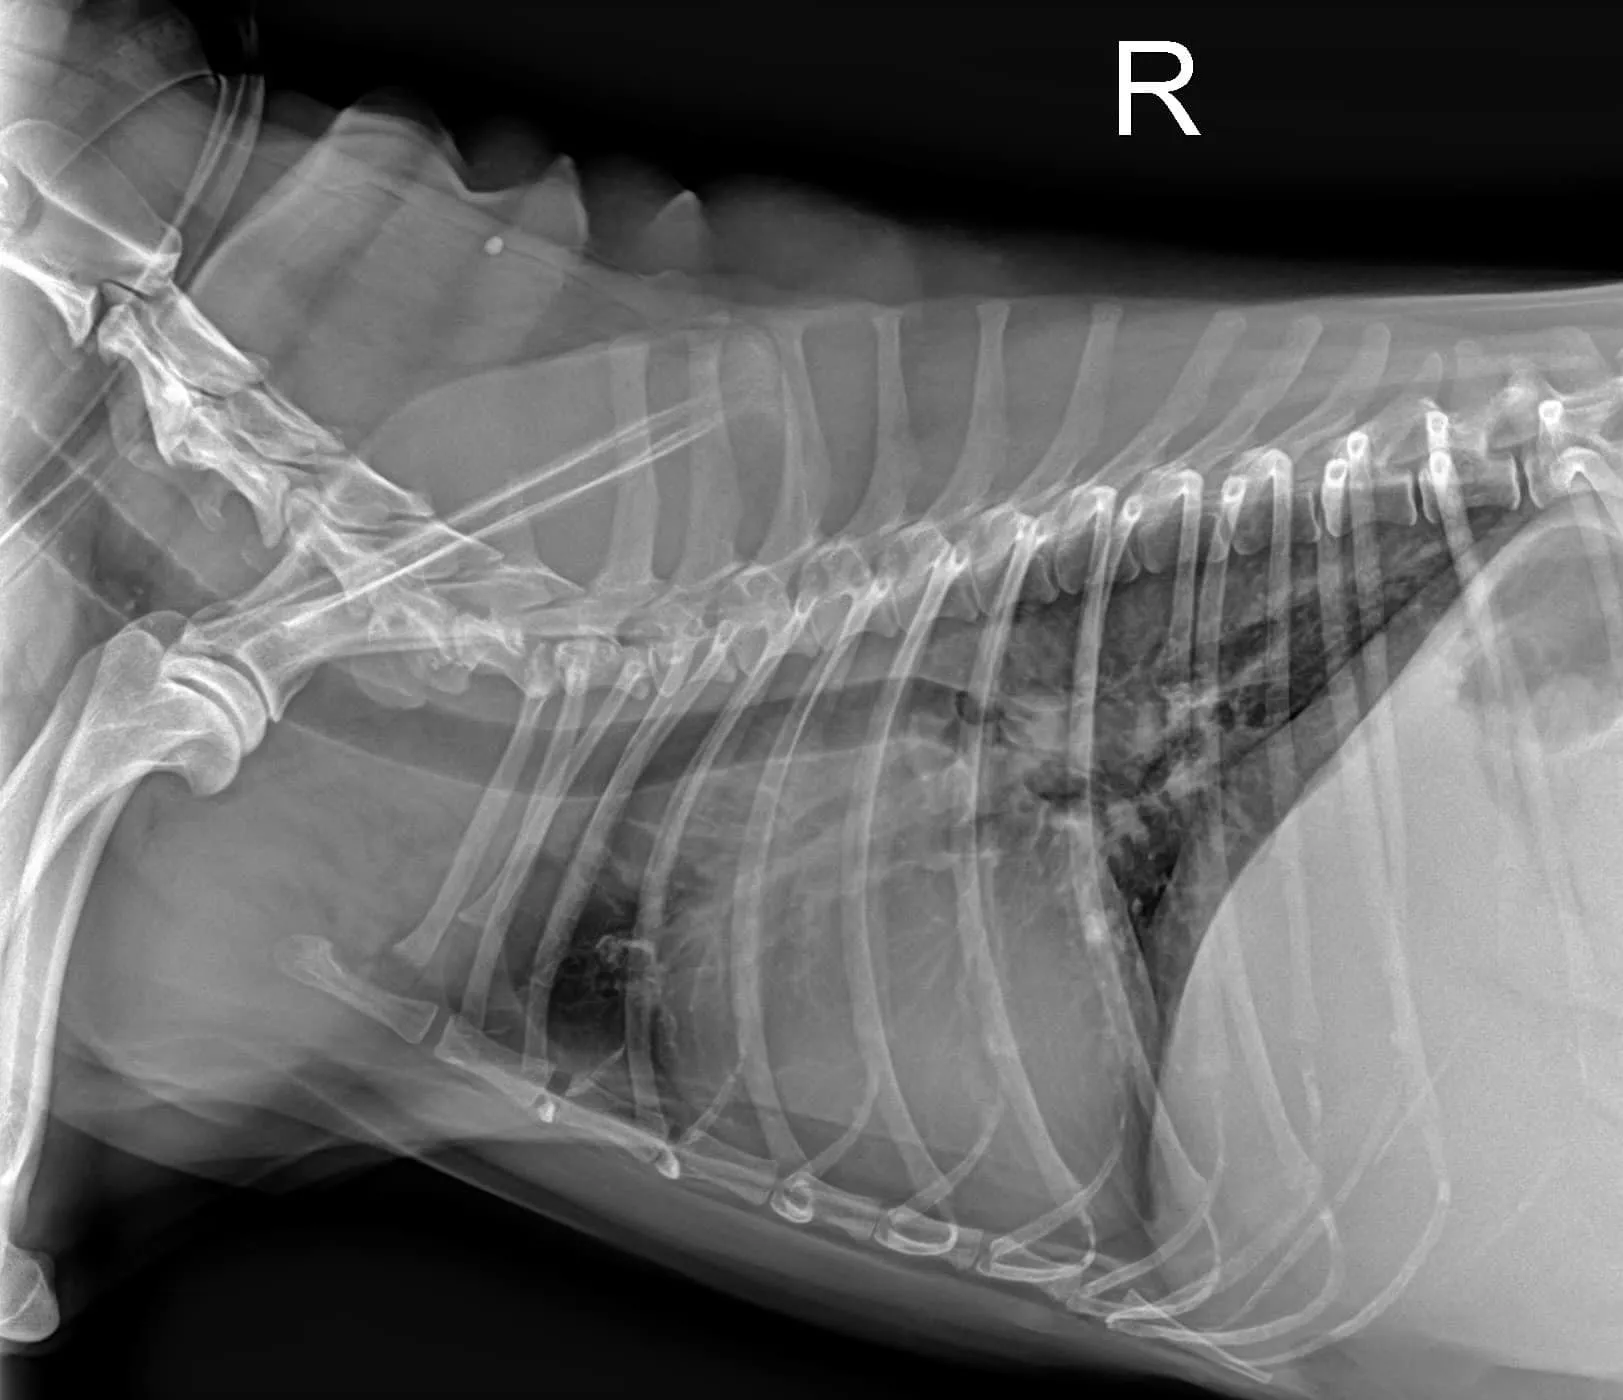

1. 突然變很喘,伴隨間斷性劇烈咳嗽。

3. 腹部異常膨脹,於友院拍攝X光,發現大量腹水。

1. 全腹部超音波檢查,發現大量腹水多且腹腔主靜脈與肝靜脈、門脈明顯擴張,但無發現腫瘤影像與淋巴腫大的問題。